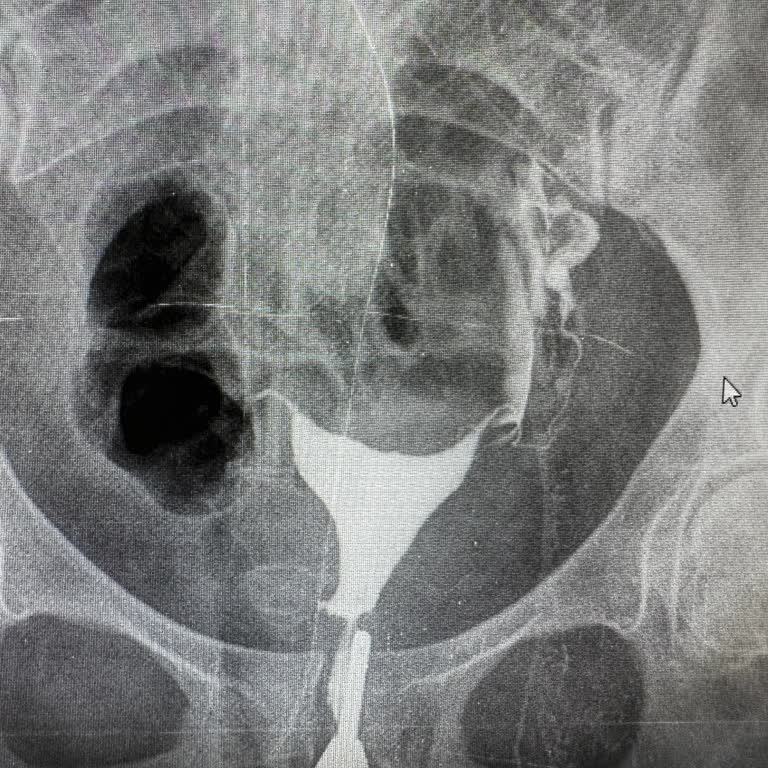

Gaziantep’te bulunan Sanko Hastanesi’nde eşim için kadın doğum bölümünde acil ameliyat olunması gerektiği söylenmesine rağmen, 07.02.2026 tarihinden bu yana özel sağlık bölümüyle hiçbir şekilde sonuç alamıyoruz. Hem telefonla hem de hastaneye bizzat giderek defalarca görüşme talebinde bulunduk; anca...